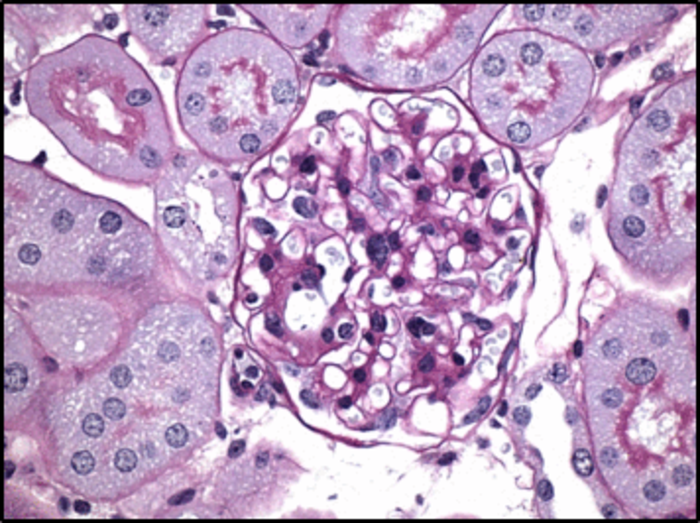

The research team also found that male and female type 1-like or type-2-like diabetic mice fed RAGE229 chow had significantly less kidney damage than mice fed control chow by several measures, including reduced inflammation-driven mesangial sclerosis – protein build-up that reduces the organs’ capacity to properly filter wastes from the bloodstream.